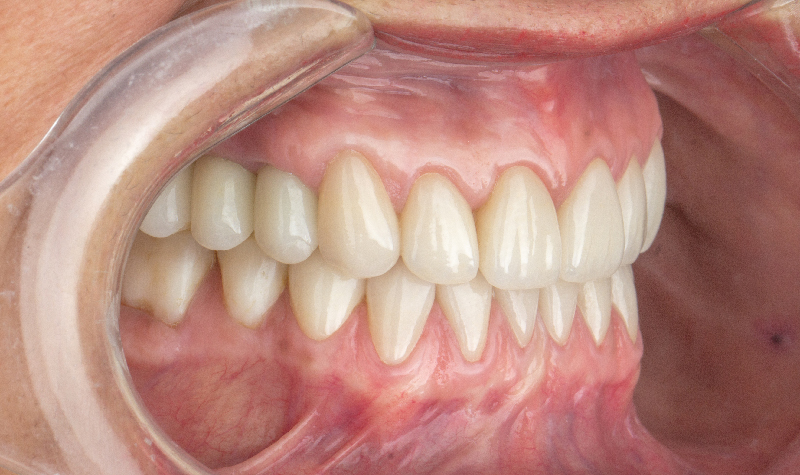

Rehabilitación oral total con prótesis inferior sobre implantes y coronas superiores.

Prótesis híbrida inferior de cerámica fija sobre implantes.

Rehabilitación oral total de alta complejidad con cerámicas sobre dientes e implantes.